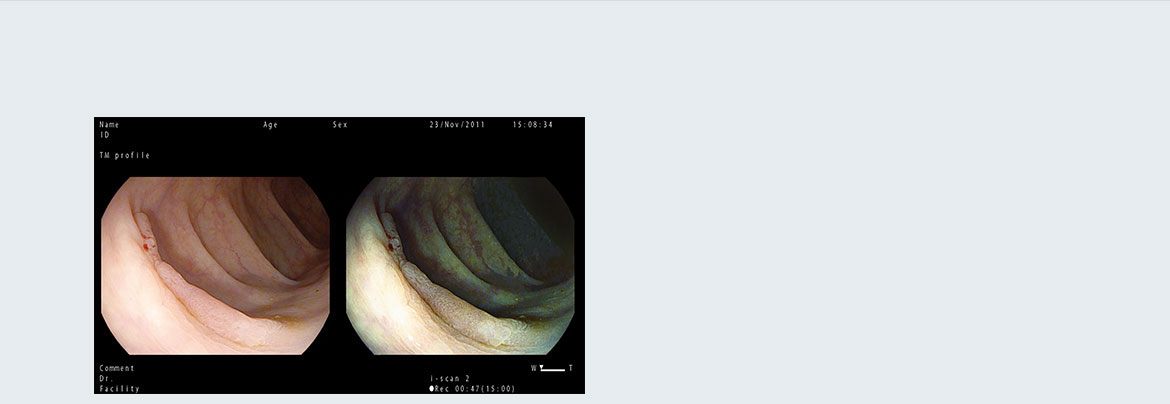

Режим одновременного показа двух изображений Twin

Два изображения одновременно на большом мониторе позволяют эндоскопистам изучать и сравнивать специфические особенности пораженных тканей, пользуясь настройками режима i‑scan и увеличением.